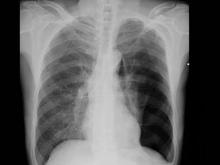

主要根據X線檢查確診。

胸部X線檢查可顯示不同程度的肺萎陷和胸膜腔積氣,有時尚伴有少量積液。

根據患者的病史、症狀體徵,以及胸部X線結果即可明確診斷。